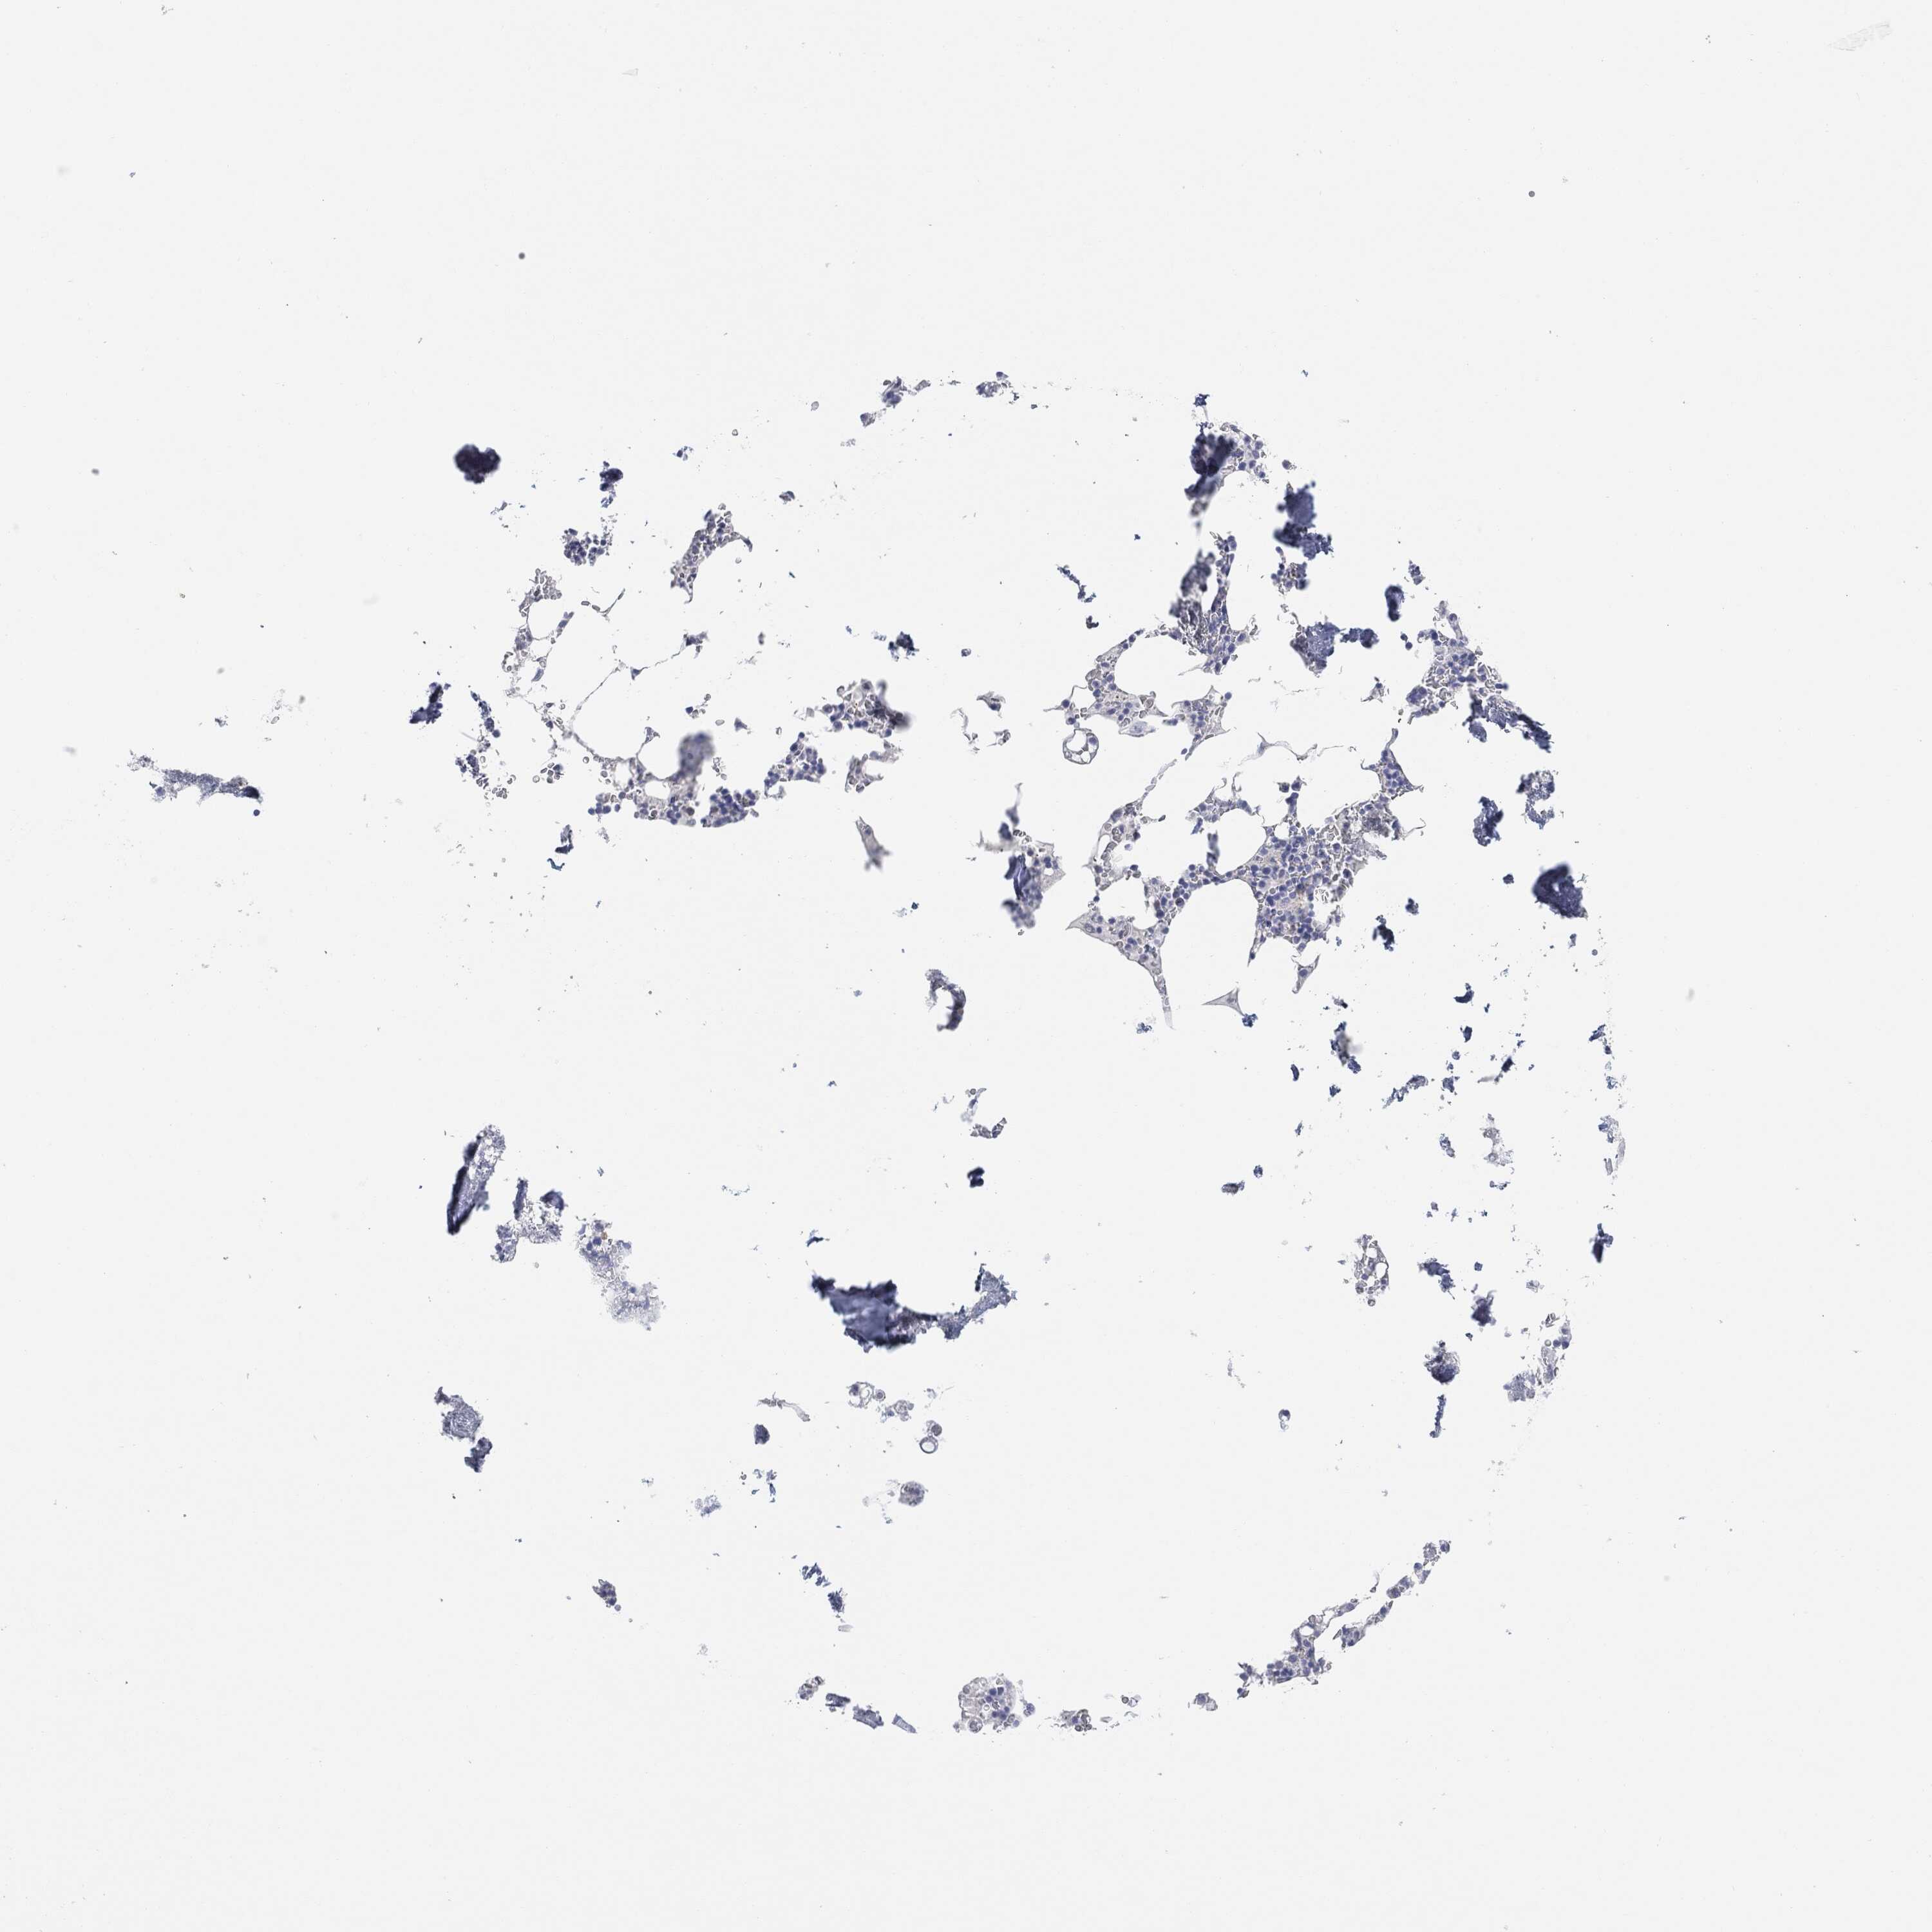

BONE MARROW - Antibody stainingi

Antibody staining in the annotated cell types in the current human tissue is reported as not detected, low, medium, or high, based on conventional immunohistochemistry profiling in selected tissues. This score is based on the combination of the staining intensity and fraction of stained cells.

Each image is clickable and will lead to virtual microscopy that enables deeper exploration of all samples and also displays staining intensity scores, fraction scores and subcellular localization as well as patient and tissue information for each sample.

Antibody HPA067508Antibody CAB080514Antibody CAB080517

Hematopoietic cells LowNot detectedLow